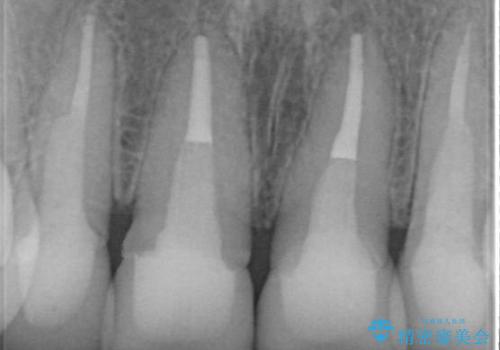

- 歯ぐきの黒っぽさ、暗い色調の前歯の改善を求めて来院されました。

金属を用いたコア・クラウンが装着されており、全ての金属を除去したのちのメタルフリー治療を計画します。